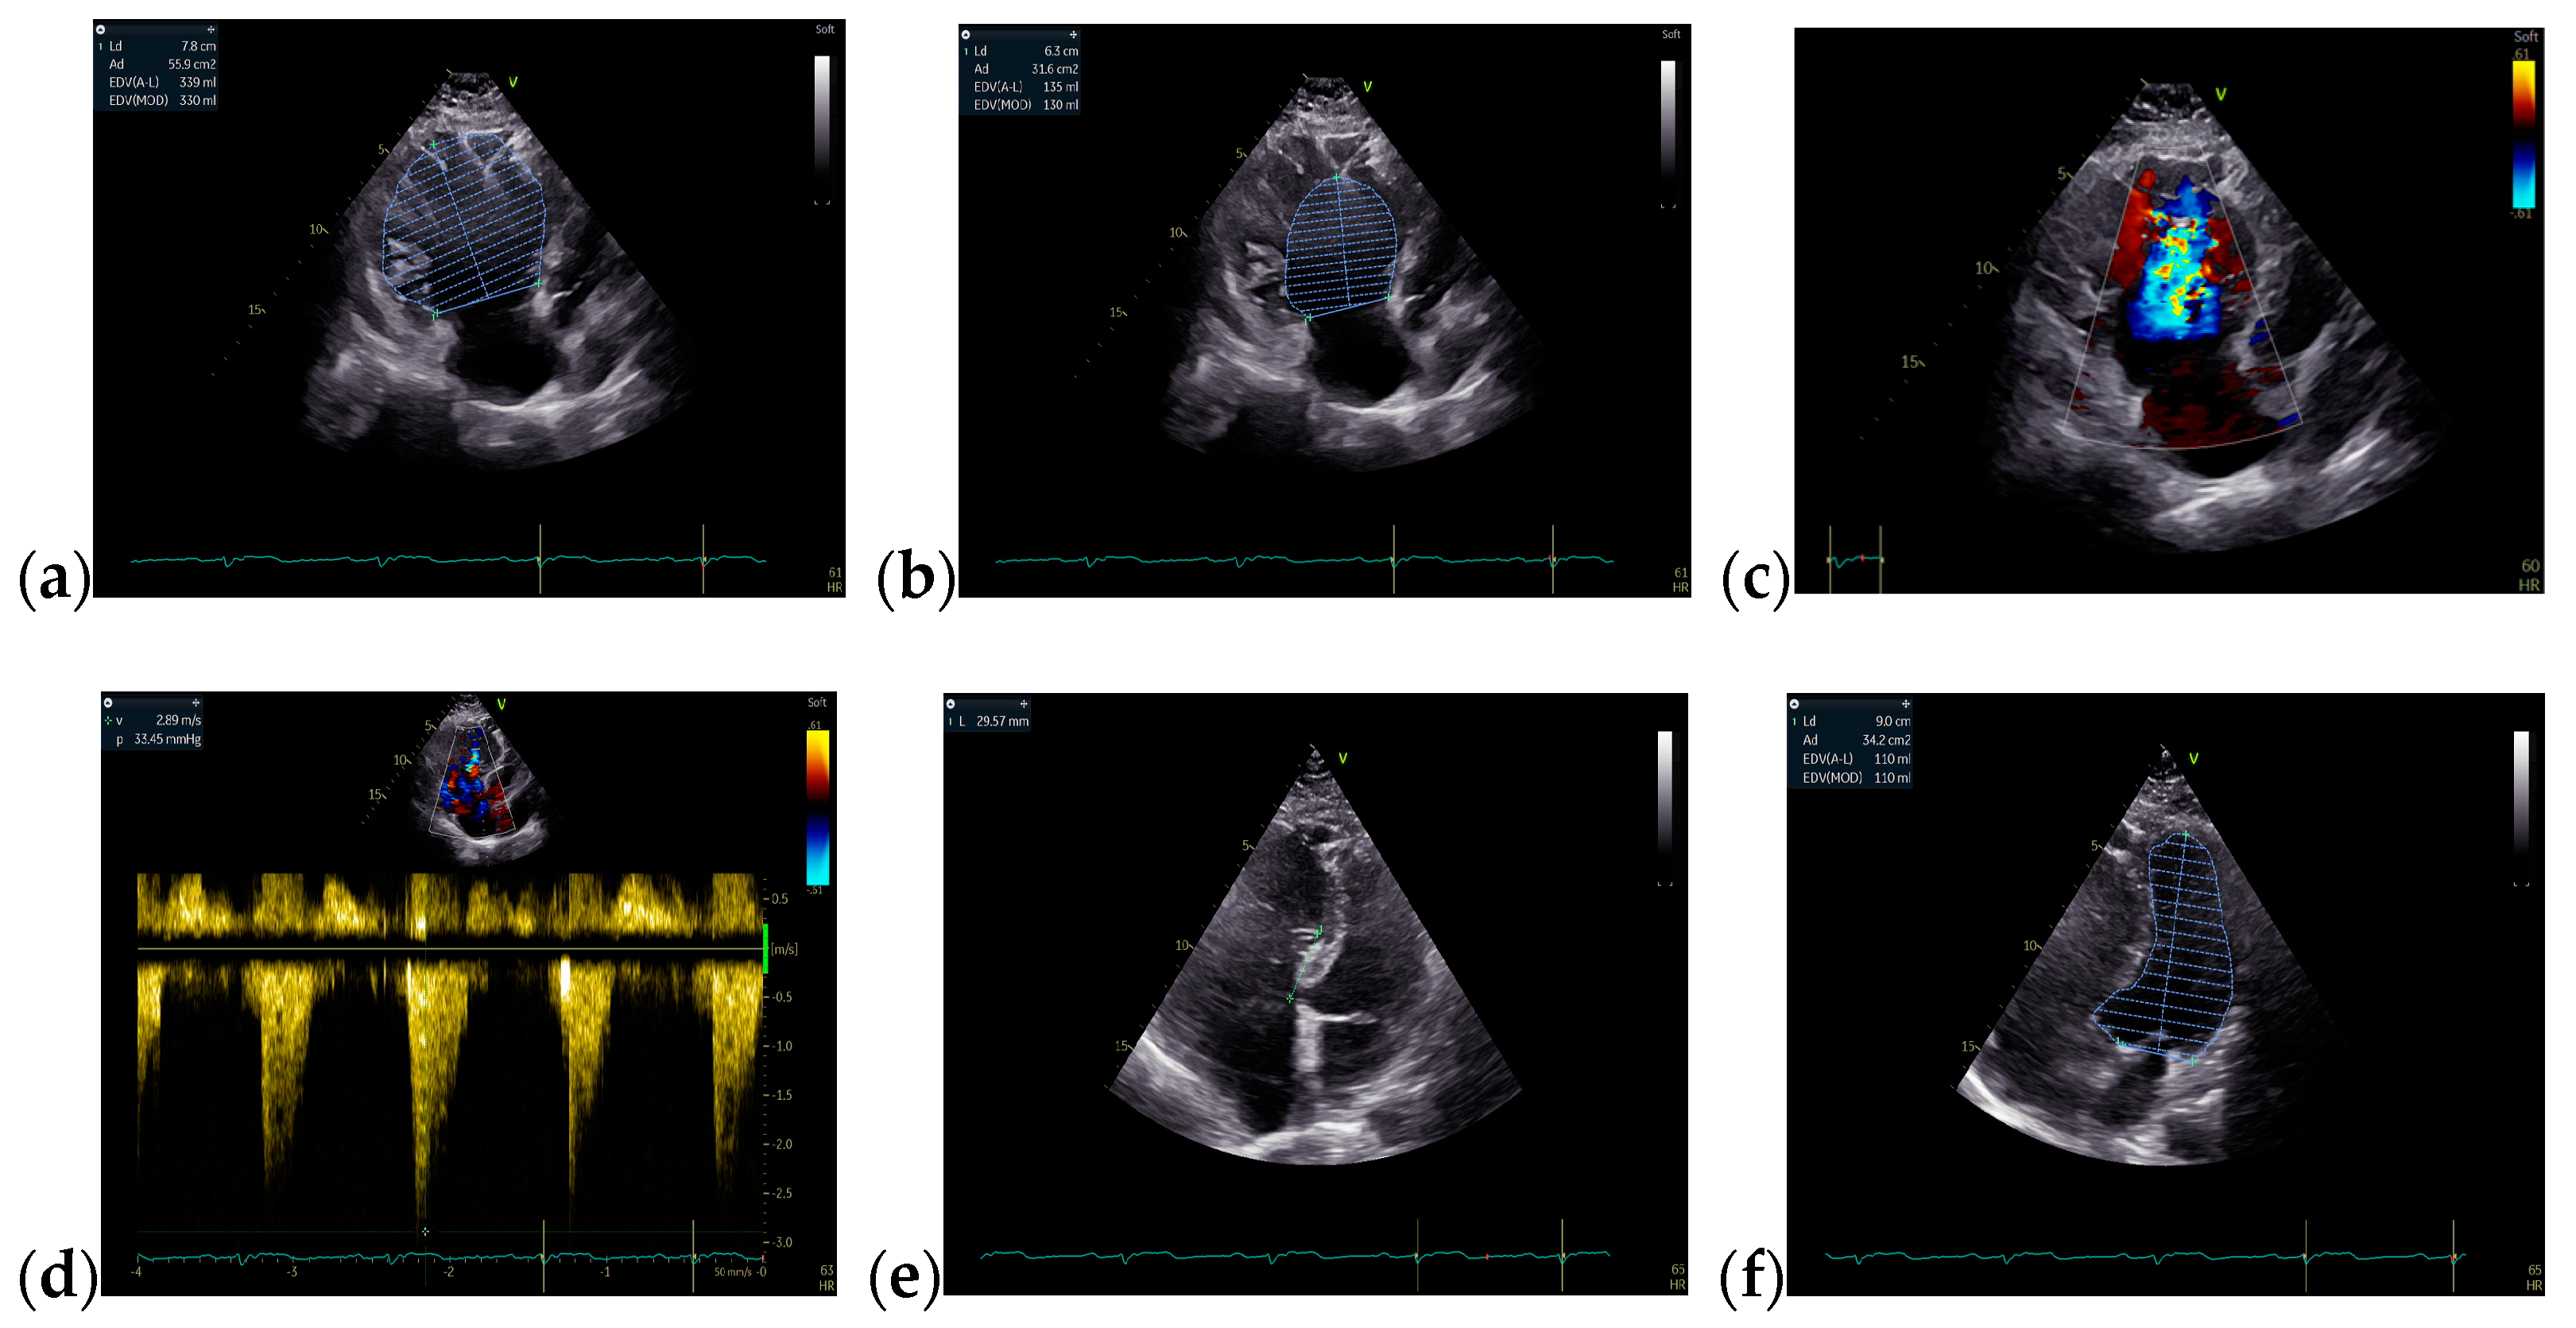

Due to the patient’s symptomatology, clinical features. and suspected findings from the TTE, including increased Qp/Qs ratio, a TOE was required and revealed an OSASD, with a diameter of 1.8 cm and aortic rim of 6.4 mm (Figure 4).

Figure 4.

TOE: (a) Mid-esophageal 4-chamber view: turbulent color Doppler flow at the level of the interatrial septum; (b) Mid-esophageal short-axis view: atrial septal defect with a diameter of 1.8 cm (18 mm); (c) Mid-esophageal short-axis view: aortic rim = 6.4 mm. Abbreviations: TOE—Transesophageal echocardiography.

Considering the hemodynamic challenges of the RV and increased Qp/Qs ratio, the recommended treatment of the defect was based on transcatheter device closure (Figure 5a). In order to establish the perfect diameter of the closing device, the diameter of the defect can be measured by ultrasound, when 25% of the determined maximum value is added, or by fluoroscopy, when 2 mm are added. Subsequently, the ASD was percutaneously closed with an ASD® Amplatzer septal occluder prostheses 9-ASD-020 without any residual shunt or complications (Figure 5b,c).

Figure 5.

Transcatheter device closure: (a,b) Fluoroscopy, measurement of the defect with a diameter of 18.5 mm; (c) implant of a 20 mm Amplatzer device.

The patient’s symptomatology improved consistently in the immediate postoperative period. Four months later, the TOE revealed the Amplatzer occluder device located at the level of the interatrial septum, with no residual shunt (Figure 6).

Figure 6.

TOE: (a) Bicaval view: the Amplatzer occluder device (b) Mid-esophageal short-axis view: Amplatzer occluder device with no residual shunt (c) 3D TOE: Amplatzer occluder device; Abbreviations: TOE—transesophageal echocardiography.